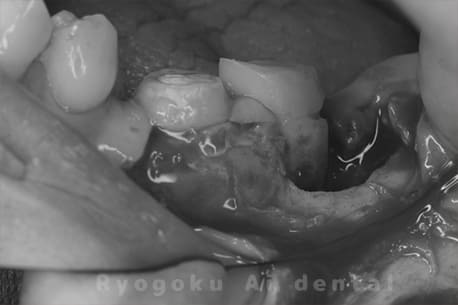

右下が腫れてた、とのことでご来院された患者様です。歯髄の炎症から歯周ポケットも深くなっておりましたが、顕微鏡下での治療で根管治療を行い、歯周ポケットも改善し、問題なく経過しております。

-

- 担当医

- Dr. 炭野